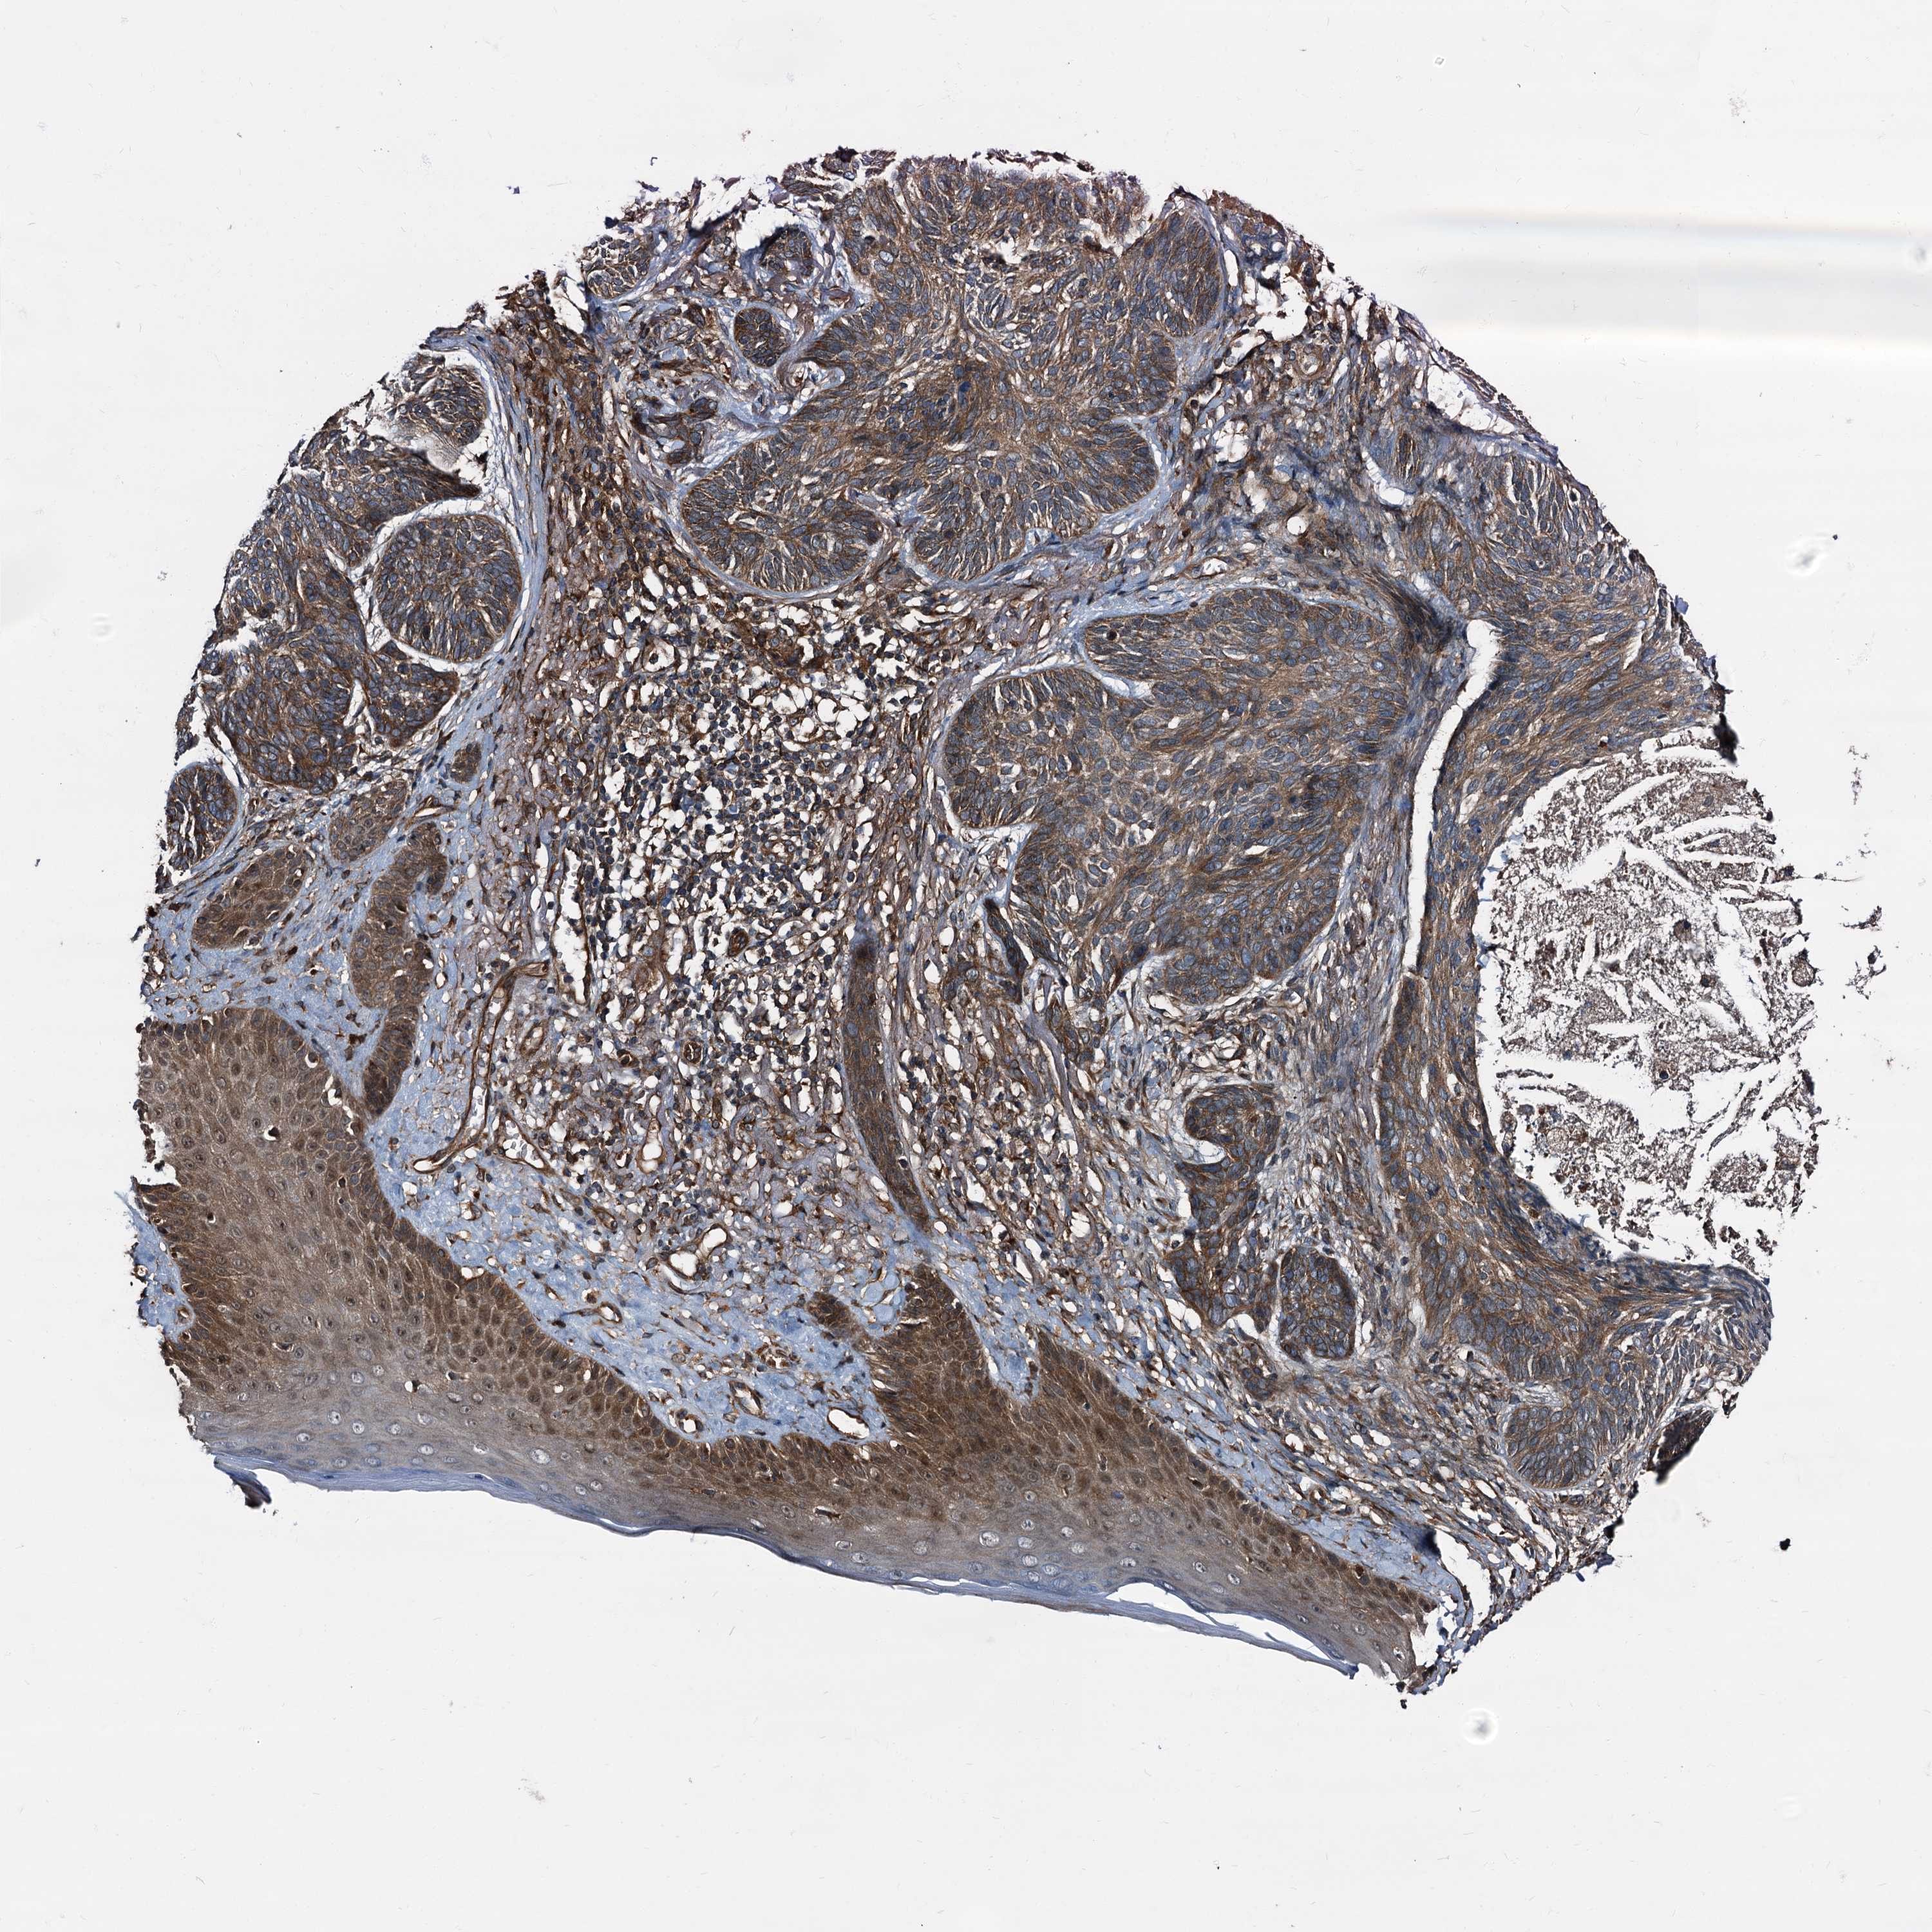

Basal cell and squamous cell cancer

SKIN CANCER - Protein expressioni

A mouse-over function shows sample information and annotation data. Click on an image to view it in a full screen mode. Samples can be filtered based on level of antibody staining by selecting one or several of the following categories: high, medium, low and not detected. The assay and annotation is described here.

Each image is clickable and will lead to virtual microscopy that enables deeper exploration of all samples and also displays staining intensity scores, fraction scores and subcellular localization as well as patient and tissue information for each sample.

Antibody HPA039259

Basal cell carcinoma

Squamous cell carcinoma, NOS

Squamous cell carcinoma, metastatic, NOS